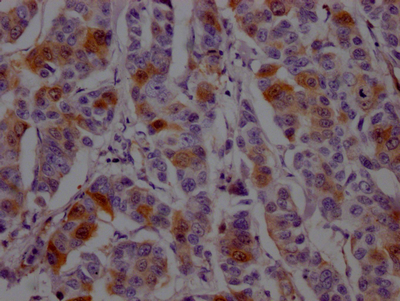

IHC image of CSB-RA264582A0HU diluted at 1:100 and staining in paraffin-embedded human liver cancer performed on a Leica BondTM system. After dewaxing and hydration, antigen retrieval was mediated by high pressure in a citrate buffer (pH 6.0). Section was blocked with 10% normal goat serum 30min at RT. Then primary antibody (1% BSA) was incubated at 4℃ overnight. The primary is detected by a Goat anti-rabbit IgG polymer labeled by HRP and visualized using 0.05% DAB.